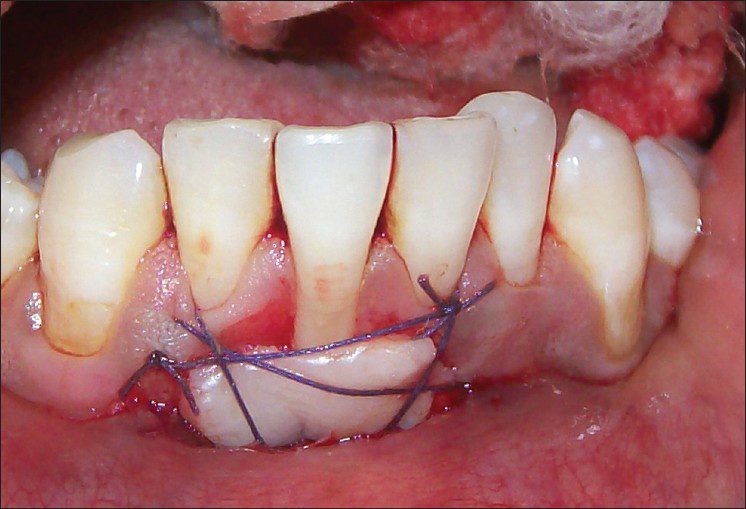

چند روز بعد از جراحی لثه بخیه کشیده میشود؟

چند روز بعد از جراحی لثه بخیه کشیده میشود؟ این سوالی است که بسیاری از بیماران پس از جراحی لثه با آن مواجه میشوند. کشیدن بخیه بعد از جراحی لثه یکی از مراحل مهم در روند بهبود است و نیازمند دقت و توجه ویژهای است. پس از جراحی لثه، معمولاً…